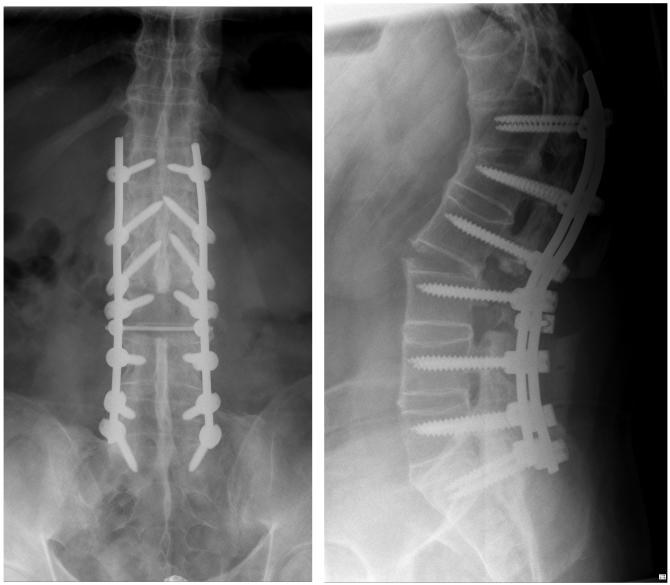

Figure 4: The conventional X-rays of the lumbar spine after the first operation in two planes (ap view left, lateral view right) show the improved position of the spine, however, compared to the intraoperative fluoroscopy (Figure 3), a partial loss of correction.

In the follow-up, we discussed how to proceed and decided to perform an additional anterior surgery. The goal was to support the anterior column of the spine and to add stability to ensure healing in a good position. Furthermore, loss of correction was observed at the postoperative standing conventional lateral X-rays compared to the intraoperatively taken fluoroscopic images. This second surgery could be performed without any problem (Figure 5 [Fig. 5]). Wound healing was uneventful, and the patient was discharged in a good condition.

Figure 5: The whole spine conventional X-rays after the second surgery reveal an improved sagittal profile, however, the initially planned and desired amount of correction has not been reached completely.